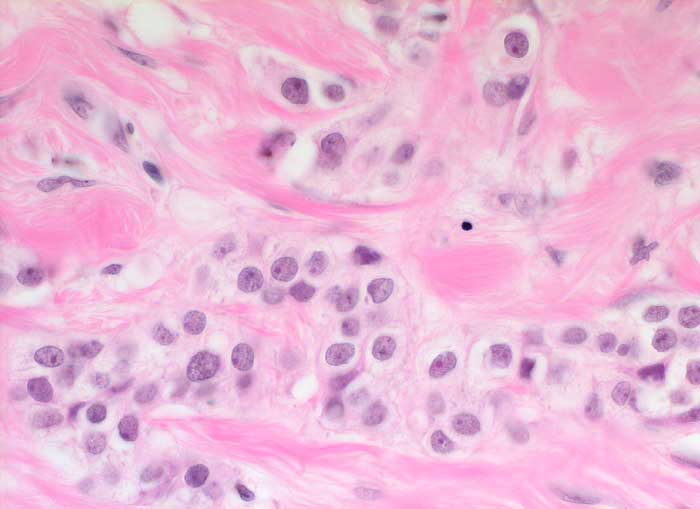

Einleitung

Das invasive Mammakarzinom zeigt zytologisch eine homogene Population maligner Zellen. Typischerweise sollten die Ausstriche zellreich sein und alle vorhandenen Zellen sollten maligne aussehen. Wenn man atypische Zellen suchen muss, ist der Ausstrich nicht diagnostisch für ein Karzinom, kann aber gleichwohl verdächtig sein. Die malignen Zellen sind in lockeren Gruppen gelagert und viele liegen einzeln. Crowding, Zellkannibalismus und Kernmolding sind gute Hinweise auf Malignität. Myoepithelien sind meistens aber nicht immer abwesend. Mammakarzinomzellen sind eher monomorph und deutlich grösser als normale duktale Epithelien. Zellkerne, die grösser sind als zwei Erythrozytendurchmesser, sind tumorverdächtig. Fast immer sind Kerbungen der Zellmembran nachweisbar. Das Chromatin ist im Gegensatz zu anderen Adenokarzinomen fein granulär und gleichmässig im Kern verteilt. Nukleolen sind meist unscheinbar. Makronukleolen sprechen für ein invasives Karzinom.

Die Kohäsivität ist das wichtigste Kriterium zur Feststellung des Differenzierungsgrades. Bei hoch differenzierten Karzinomen finden sich Verbände, bei wenig differenzierten liegen die Tumorzellen vermehrt einzeln. Wenig differenzierte Karzinome zeigen gesteigerte Kernatypien und der Hintergrund ist eher detritisch aufgrund ausgedehnter Tumornekrosen.

Unten werden Beispiele von einem hochdifferenzierten und einem wenig differenzierten Mammakarzinom gezeigt.